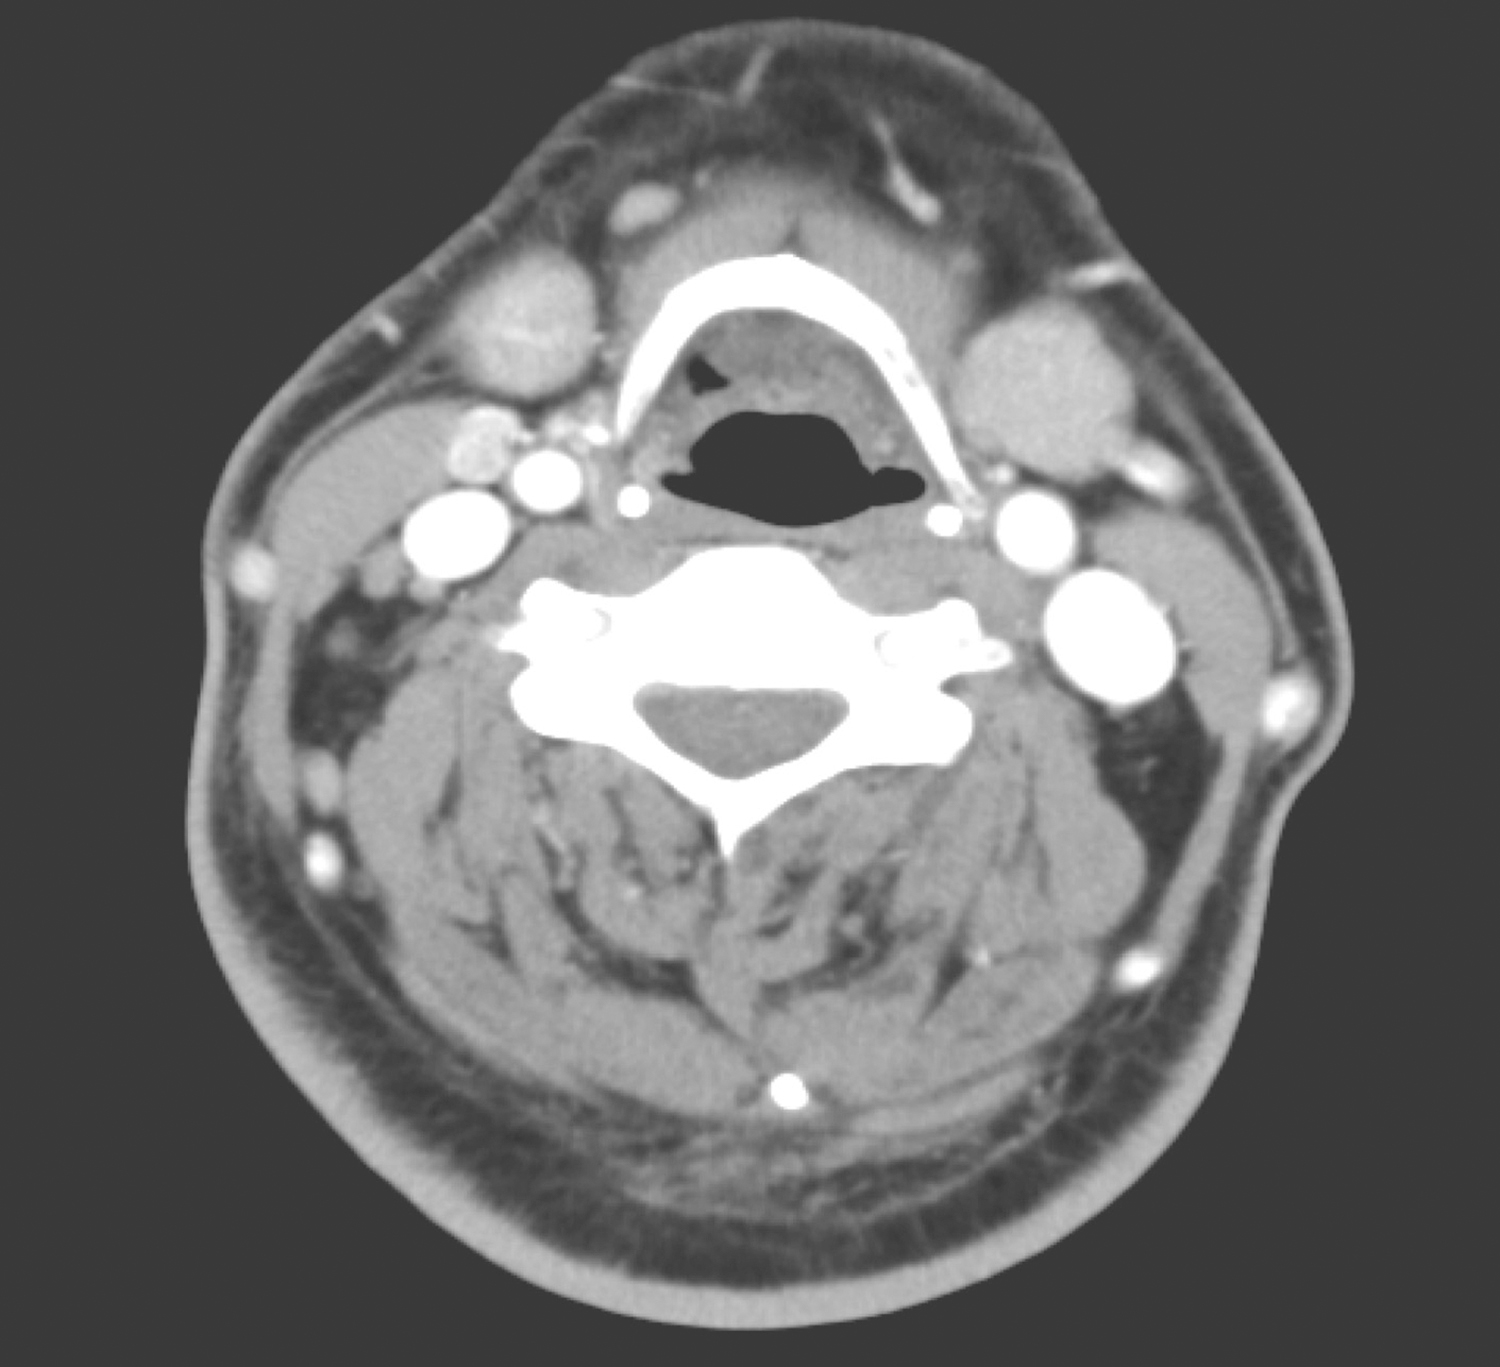

双颈深、右下颈甲状腺旁、双侧锁骨上、气管前、可见多发淋巴结肿大,部分明显强化,大者约1.2cm×0.9cm(图4~图6);余颈未见明显肿大淋巴结。

图5 颈部增强CT示双颈多发肿大淋巴结

图6 颈部增强CT示气管前及锁骨上肿大淋巴结